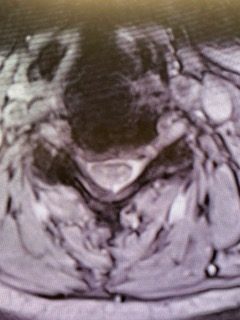

Current imaging studies (Figs. 1 and 2) demonstrated significant degenerative collapse of C45 segment, retrolisthesis and with severe right foraminal stenosis as well as C3-4 degenerative disc degeneration with moderate compression of thecal sac. Patient failed conservative management and it was decided, given her prior two anterior procedures, that an excellent decompression could be accomplished with a posterior laminectomy, foraminotomy and fusion to maintain alignment.

(Fig. 2) Axial T2 cervical MRI at C4-5 demonstrating significant osteophytic disease with bilateral neural foraminal compression of the C5 nerve roots, right greater than left.